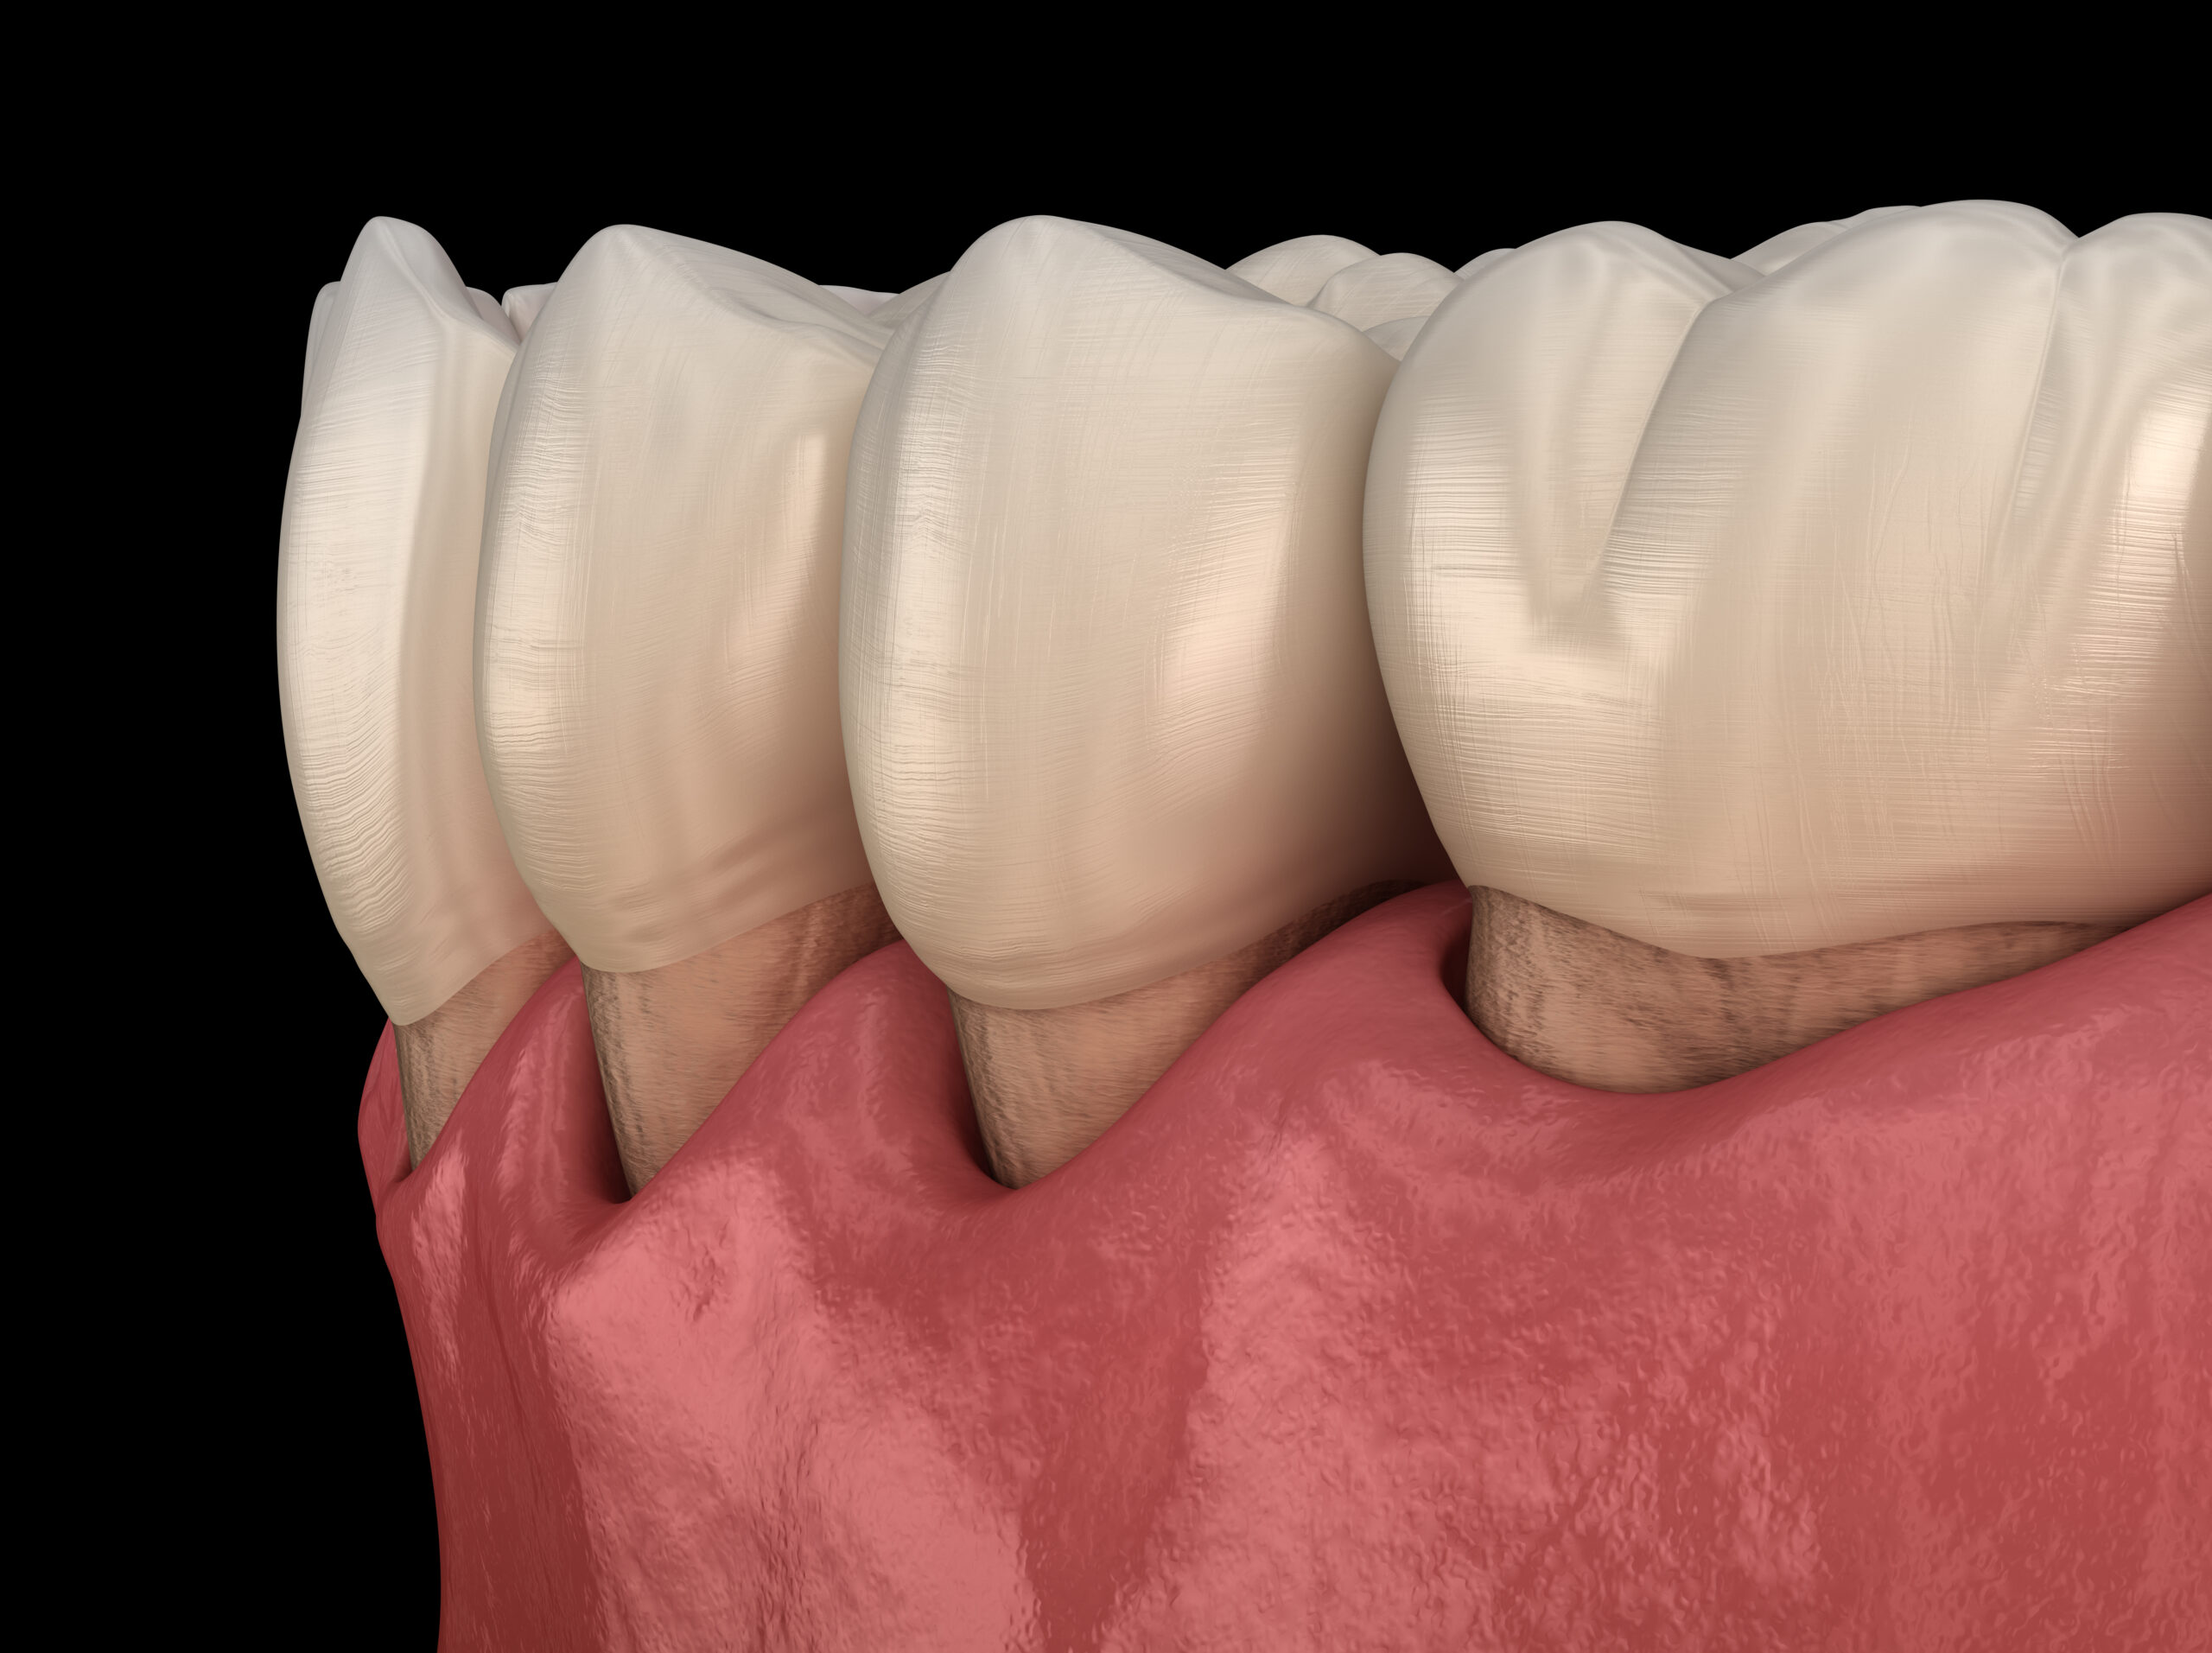

It may not be easy to spot receding gums at first. However, once the gums pull back too much, it becomes readily apparent and requires

One of the most common symptoms of periodontal disease is gum recession. This occurs when the gum tissue begins to pull back from the teeth,

Gum recession potentially leads to problems with your oral health, including tooth decay, missing teeth and infections. Traditionally, periodontists treated advanced gum disease and recession

When assessing your smile, there are several factors that can make you look older than you are, such as stained or misshapen teeth, missing teeth,